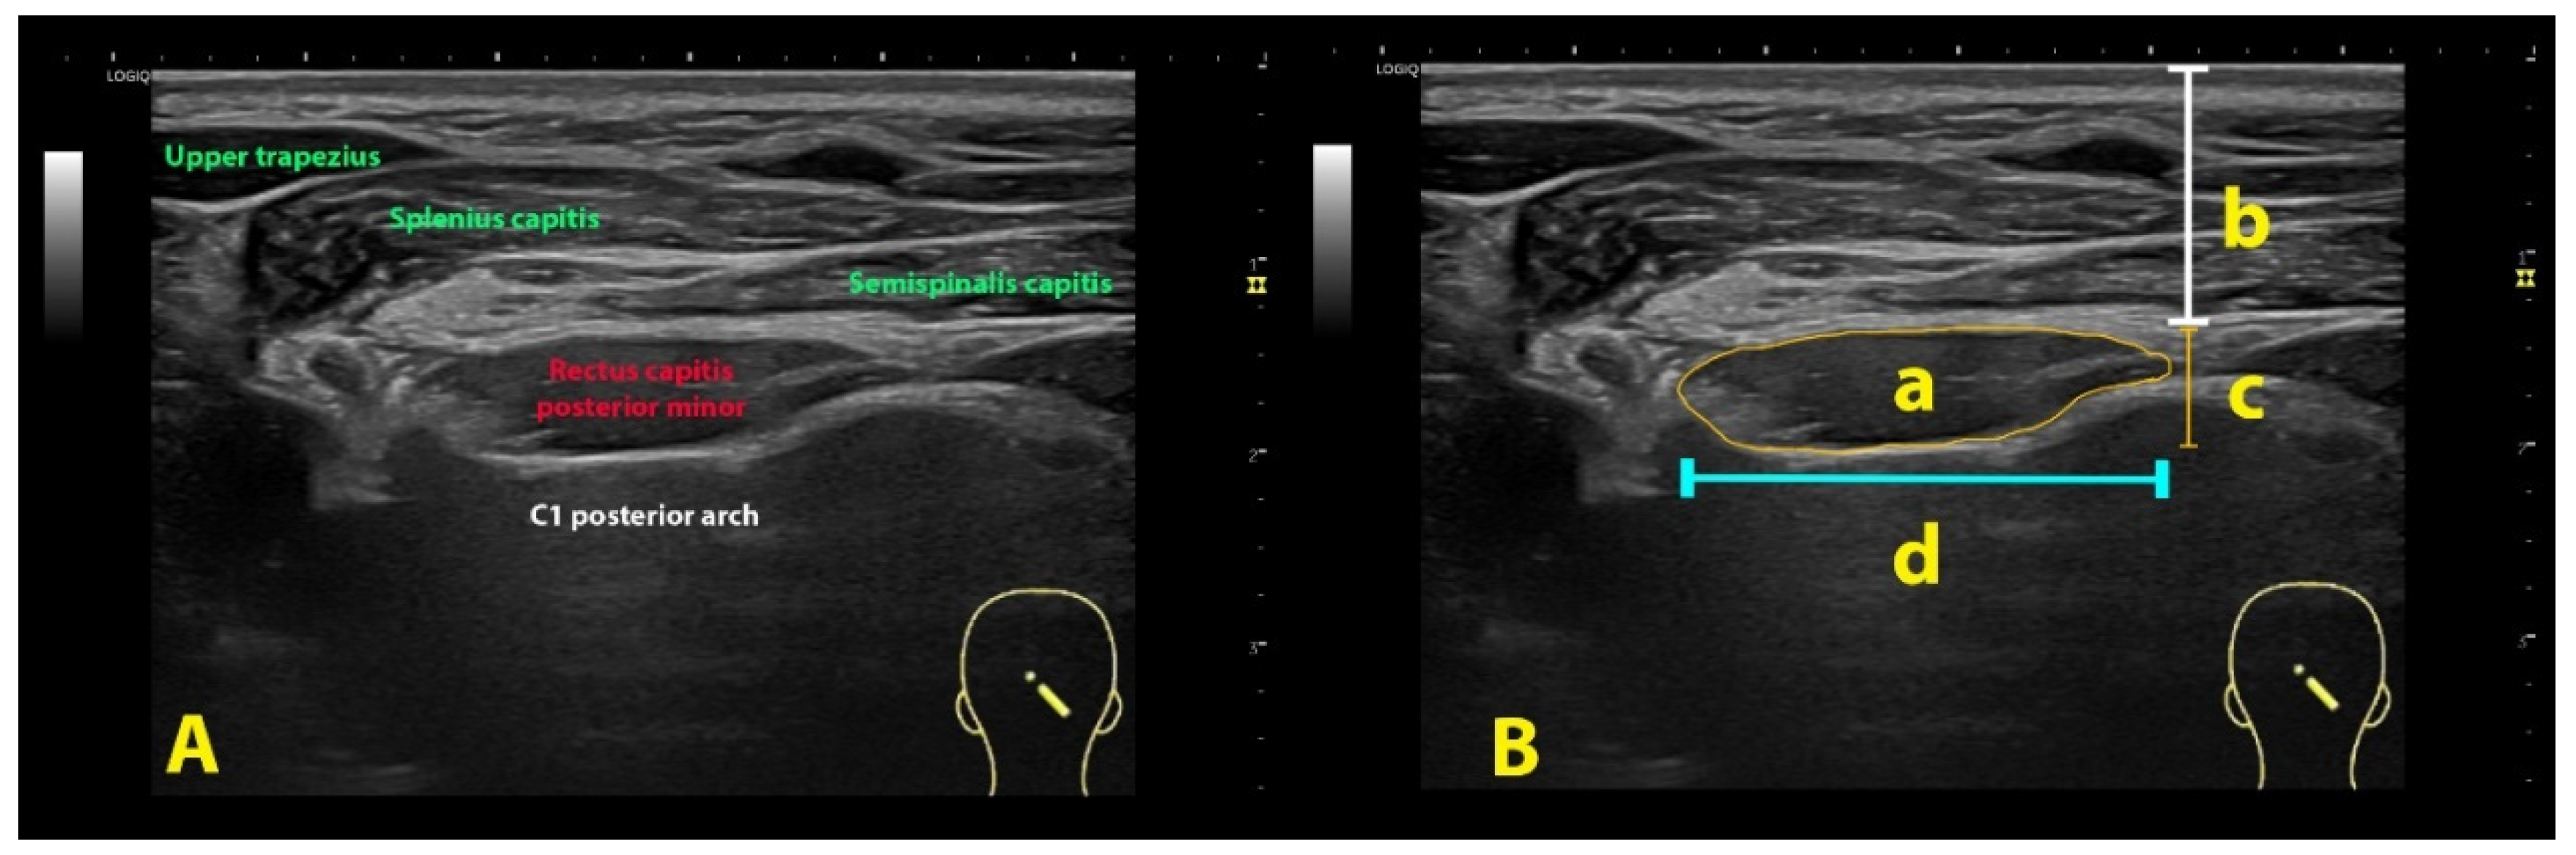

- Error in Figures